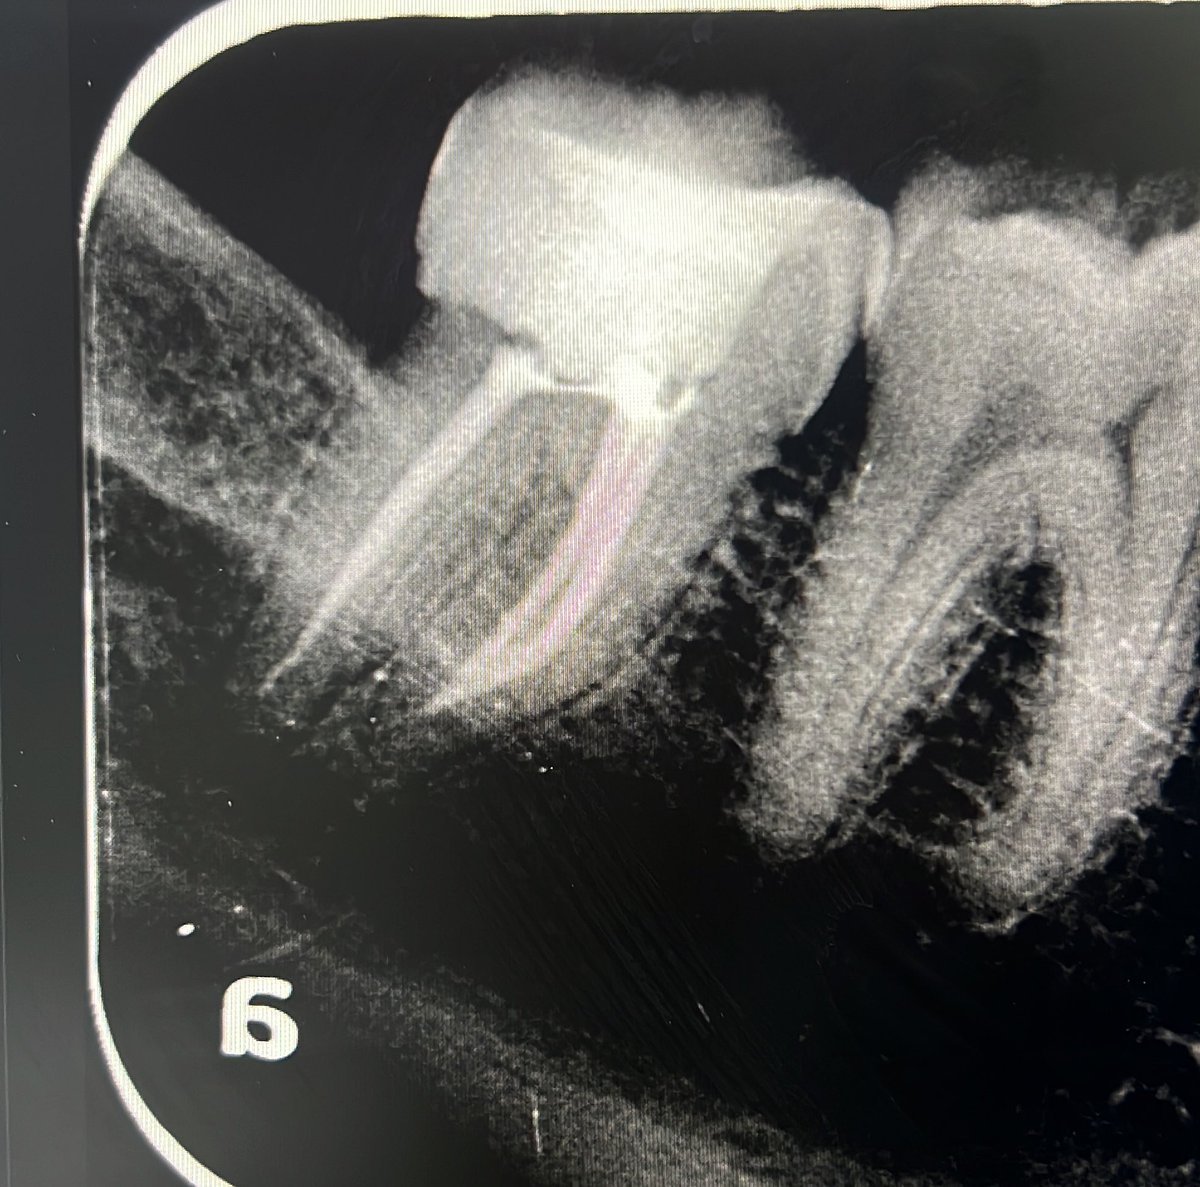

Today’s case:

Rct of #11 Dx : PI/AAA

• 1st visit: Open access, irrigation, abscess drainage, and dressing the canal with Ca(OH)₂.

• 2nd visit (after 30 days): Reopening the tooth, irrigation performed; the canal was completely dry and ready for obturation.

Patient is fine😁